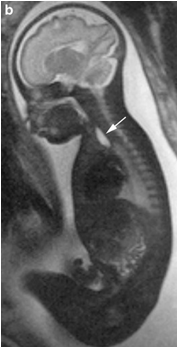

◇ MRI

明确的超声诊断依据

食道扩张盲端

羊水过多

无正常胃泡影